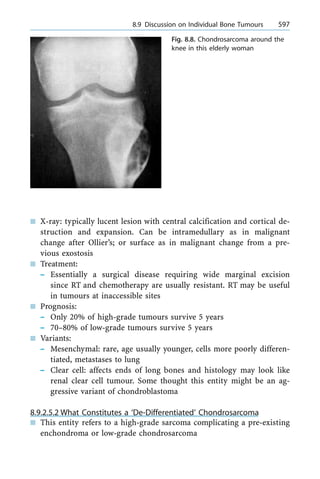

n Malunited fracture

3.6.6.1 Really Undisplaced Fracture

n Refer to definition of undisplaced

n Treatment ± many studies indicate only 4±5% nonunion even with

simple casting

n Methods of casting ± long versus short arm reported in literature with

no statistical difference, some experts like Barton had suggested can

a 3.6 Scaphoid Injuries 249

do away with thumb spica part ± however, most surgeons still use the

traditional teaching of Bohler, i.e. immobilise the thumb as well dur-